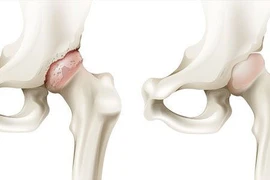

SuperPath là một trong kỹ thuật thay khớp háng tiên tiến nhất hiện nay. Phương pháp này được chỉ định phẫu thuật rộng rãi các bệnh lý khớp háng khác nhau như: hoại tử chỏm xương đùi, thoái hóa khớp háng, gãy cổ xương đùi...